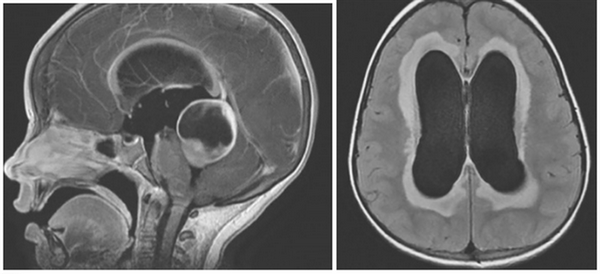

Исходя и механизма развития, водянка головного мозга бывает:

- открытой (сообщающаяся);

- закрытой (окклюзионная).

Внутренняя тривентрикулярная окклюзионная гидроцефалия на МРТ во фронтальной и сагиттальной плоскостях: на левом снимке видно гигантское кистозно-солидное образование, явившееся причиной обструкции ликворопроводящих путей на уровне Сильвиева водопровода

МРТ покажет гидроцефалию?

При магнитно-резонансной томографии получают послойные снимки исследуемой анатомической области. При изучении сканов врач видит мозговое вещество и выявляет отклонения от нормы. МРТ отчетливо показывает гидроцефалию. Метод информативен на ранних этапах развития заболевания, даже при отсутствии у пациента характерных симптомов. Детализация снимков позволяет врачам выявить водянку головного мозга, определить тип, диагностировать сопутствующие заболевания.

Водянка головного мозга при МР-сканировании в коронарной проекции